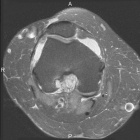

P.P. - 55 year old female c/o right knee pain x 1.5 years. Pain is dull, intermittent, worse with activity. No mechanical symptoms. No history of trauma. Treatment with NSAIDs, aspirations, viscosupplementation, intraarticular steroids provide minimal relief.

Zoom image: Radiological image Radiological image.